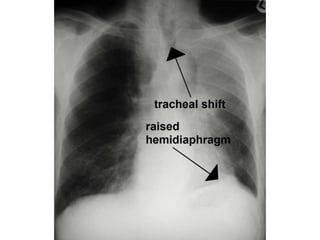

The term collapseis used when a whole lobe or lung is involved. Atelectesis is defined as diminished volume affecting all or part of a lung, whichmay or may not include loss of normal lucency in the affected part of lung . Pulmonary atelectasis can be divided into six types, based on mechanism: resorptive, adhesive, compressive, passive, cicatrization, and gravity- dependent

LOBAR ATELECTASIS Radiologic signsof lobar atelectasis :- Direct or Indirect . Direct signs include increased opacification of the airless lobe and displacement of fissures.

Indirect signs includedisplacement of hilar and cardiomediastinal structures toward the side of collapse, narrowing of the ipsilateral intercostal spaces, elevation of the ipsilateral hemidiaphragm, compensatory hyperinflation and hyperlucency of the remaining aerated lung, and obscuration or desilhouetting of the structures adjacent to the collapsed lung (eg, diaphragm and heart borders). Additional radiologic features vary according to the site of atelectasis.